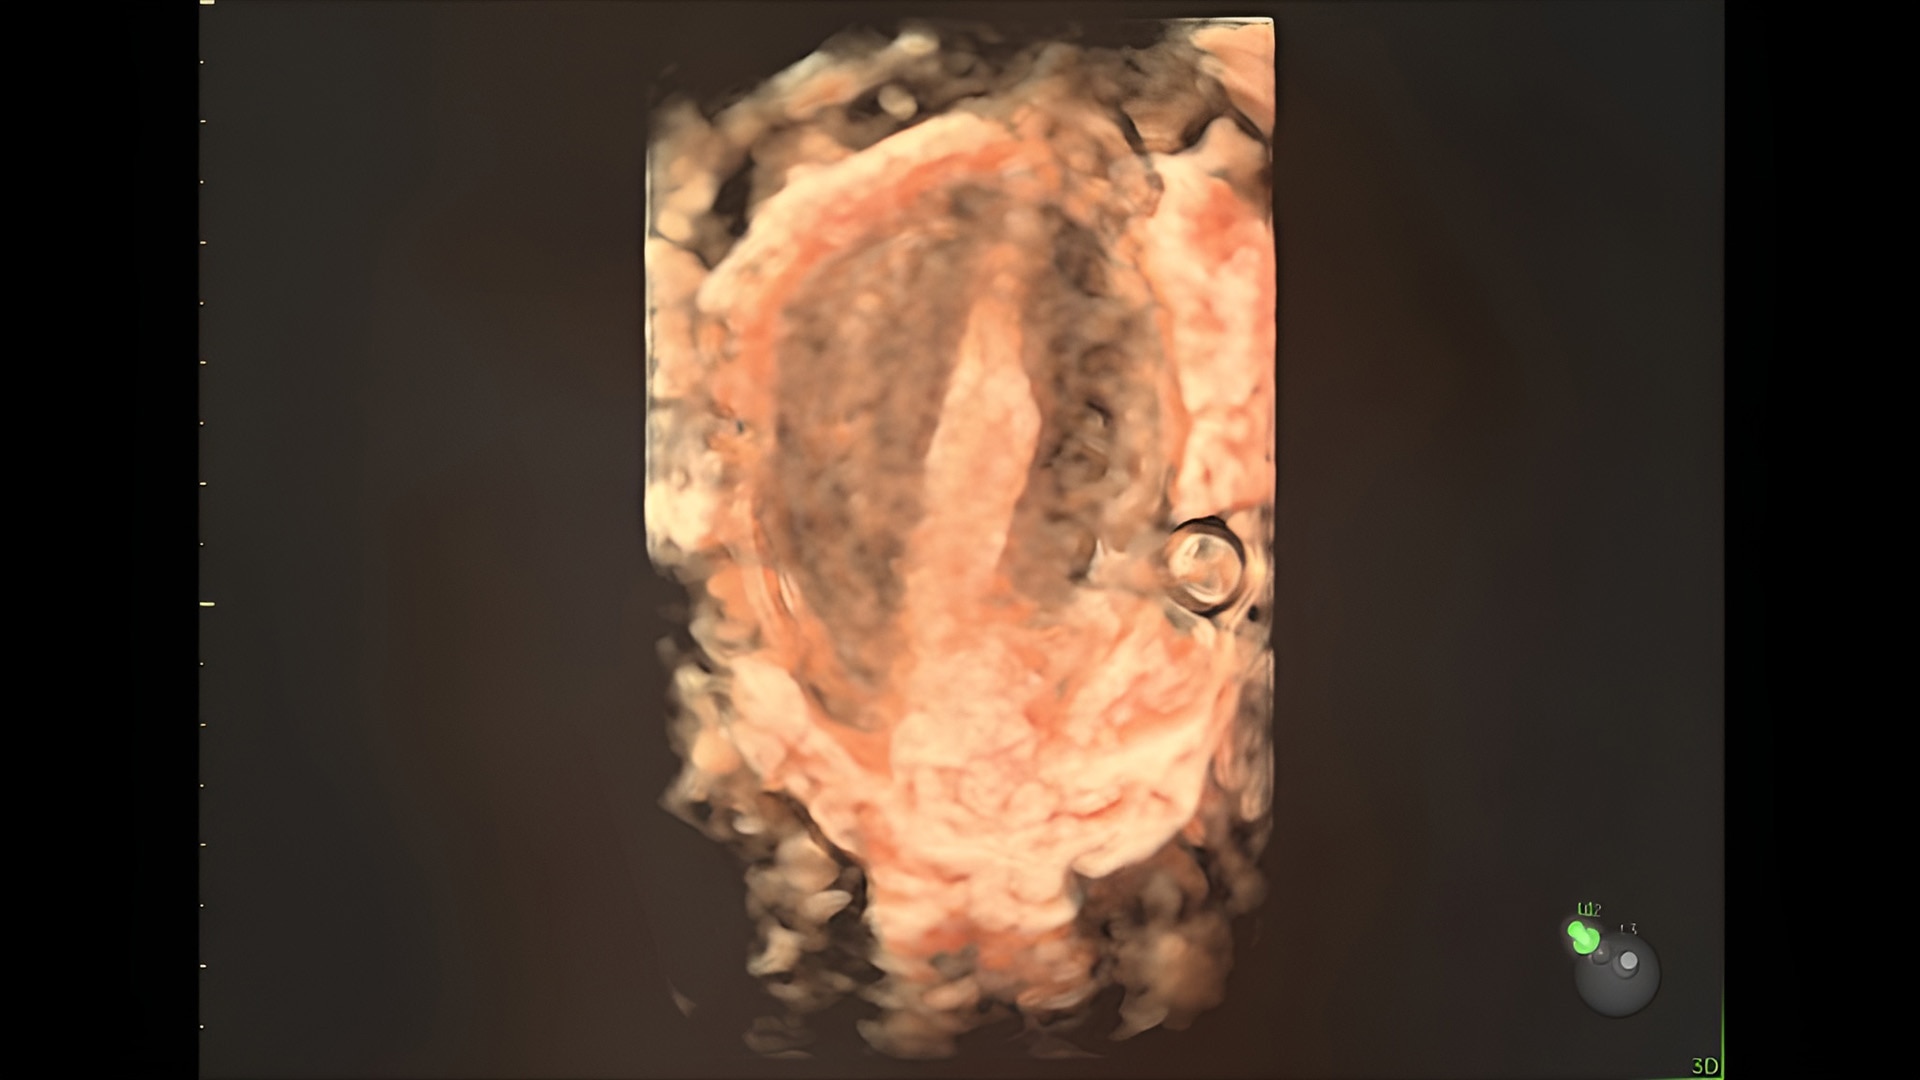

Discover complicated anomalies and pathologies with the Voluson Expert 22 to provide answers sooner for better decision making.

Complex cases come with enough uncertainty. That's why the Voluson Expert 22 is specifically designed for in-depth assessment of complicated anatomy — with pioneering first trimester, fetal cardiac, gynecological, and other pivotal technologies that focus on early detection and intervention.

First trimester exams

Perform detailed exams with high-resolution for early insights to fetal health